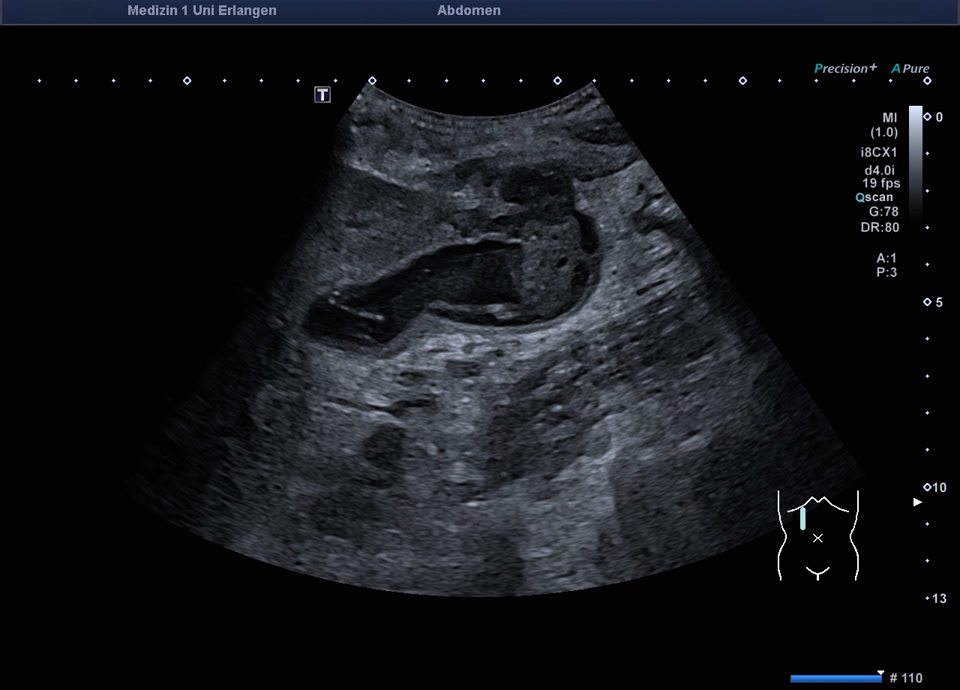

Ultraschall in der Notaufnahme: Gallenblasenempyem mit gedeckter Perforation